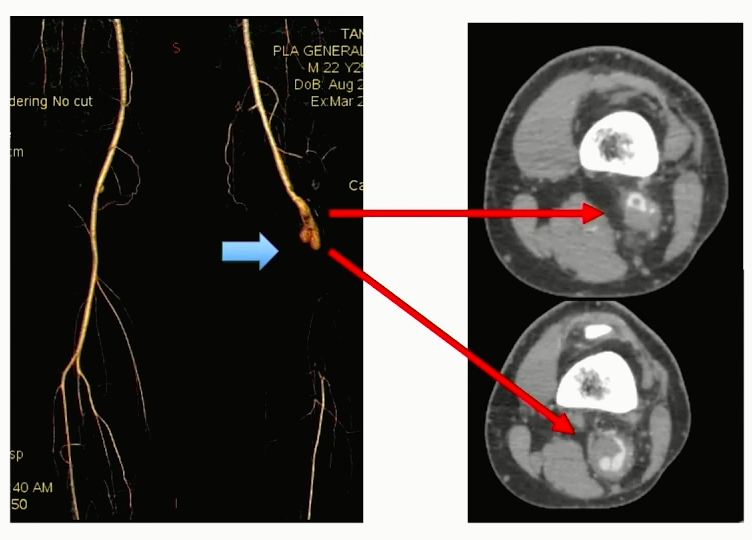

患者信息:男,22岁

现病史:突发左小腿疼痛,足趾发凉,感觉迟钝,运动受限3天

查体:

①踝部运动受限,肌力4级;

②足背及足趾散在花斑;

③足背及胫后动脉无法触及;

④腘窝触及7cm×4cm包块,搏动不清

既往史:2017年诊断“脉管炎”行药物灌注;2018年行“左侧腘动脉瘤切除+大隐静脉置换术”;2020年行“急性左下肢动脉栓塞切开取栓+左侧小腿筋膜切开减压”

CTA:左侧腘动脉假性动脉瘤,动脉瘤以远血管闭塞,远端仅可见腓动脉及显影模糊的胫前动脉

诊断:左侧腘动脉假性动脉瘤伴远端闭塞